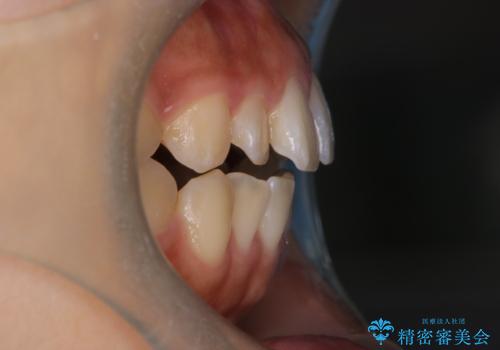

- 前歯の叢生を主訴に来院されました。非抜歯でインビザラインで治療をしました。

叢生はIPRをし、並べました。この患者様はオープンバイトだったため歯を並べる過程でかみ合わせも治しました。